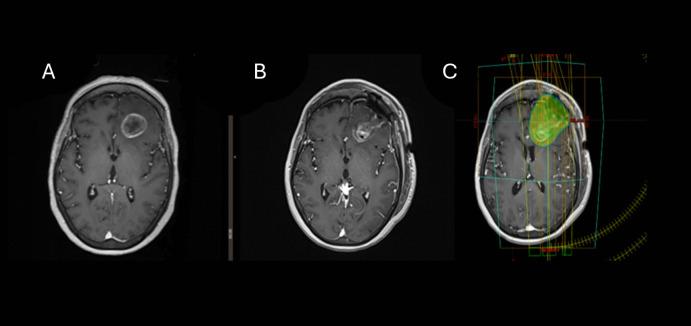

Breast cancer brain metastases (BCBM) are increasingly common due to improved systemic therapies prolonging survival. This study evaluates local control and factors influencing outcomes in patients with resected BCBM treated with postoperative stereotactic radiotherapy (SRT).

METHODS

A retrospective review included single resected BCBM treated with postoperative SRT from 2010 to 2022. The median follow-up was 28 months (range, 14-43). Variables analyzed included tumor size, biology, surgical corridor inclusion, radiation dose, and timing of SRT. Multivariable analysis was conducted using Cox regression.

62 patients were analyzed in multivariable analysis, HER2-positive status was associated with improved local control (HR: 0.76, 95% CI: 0.36-0.88, p = 0.032), as was a higher biologically effective dose (BED > 40 Gy, HR: 0.65, 95% CI: 0.45-0.89, p = 0.028). In contrast, tumor size > 5 cm (HR: 2.1, 95% CI: 1.7-4.6, p = 0.021) and delayed initiation of SRT beyond 28 days post-surgery (HR: 2.7, 95% CI: 1.9-4.7, p = 0.015) were associated with worse outcomes. Age, cystic metastases, inclusion of surgical corridor, and tumor location were not significantly related to local control. Radiation necrosis occurred in 13% of patients, predominantly asymptomatic.

由于全身治疗的改善延长了生存期,乳腺癌脑转移(BCBM)越来越常见。本研究评估了接受术后立体定向放射治疗(SRT)的切除性BCBM患者的局部控制情况及影响预后的因素。

一项回顾性研究纳入了2010年至2022年接受术后SRT治疗的单发切除性BCBM患者。中位随访时间为28个月(范围14 - 43个月)。分析的变量包括肿瘤大小、生物学特性、手术通道包含情况、放射剂量和SRT的时机。使用Cox回归进行多变量分析。

多变量分析纳入了62例患者,HER2阳性状态与更好的局部控制相关(风险比:0.76,95%置信区间:0.36 - 0.88,p = 0.032),更高的生物学有效剂量(BED > 40 Gy,风险比:0.65,95%置信区间:0.45 - 0.89,p = 0.028)也是如此。相比之下,肿瘤大小> 5 cm(风险比:2.1,95%置信区间:1.7 - 4.6,p = 0.021)以及术后28天以后延迟开始SRT(风险比:2.7,95%置信区间:1.9 - 4.7,p = 0.015)与更差的预后相关。年龄、囊性转移、手术通道包含情况和肿瘤位置与局部控制无显著相关性。13%的患者发生放射性坏死,主要为无症状性。